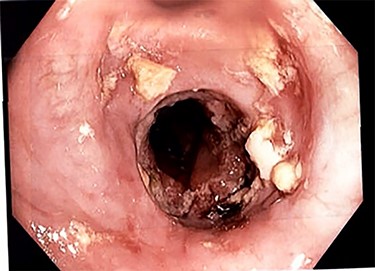

Due to inadequate oral intake and weight loss, an upper gastrointestinal endoscopy was performed 1 year later. An anastomotic stricture was objectified, for which a stent was installed (Fig. 3). The stent was removed 6 weeks later, and the width of the anastomosis was appropriate (Fig. 4).

Esophagojejunal anastomosis after removal of the endoscopic stent.